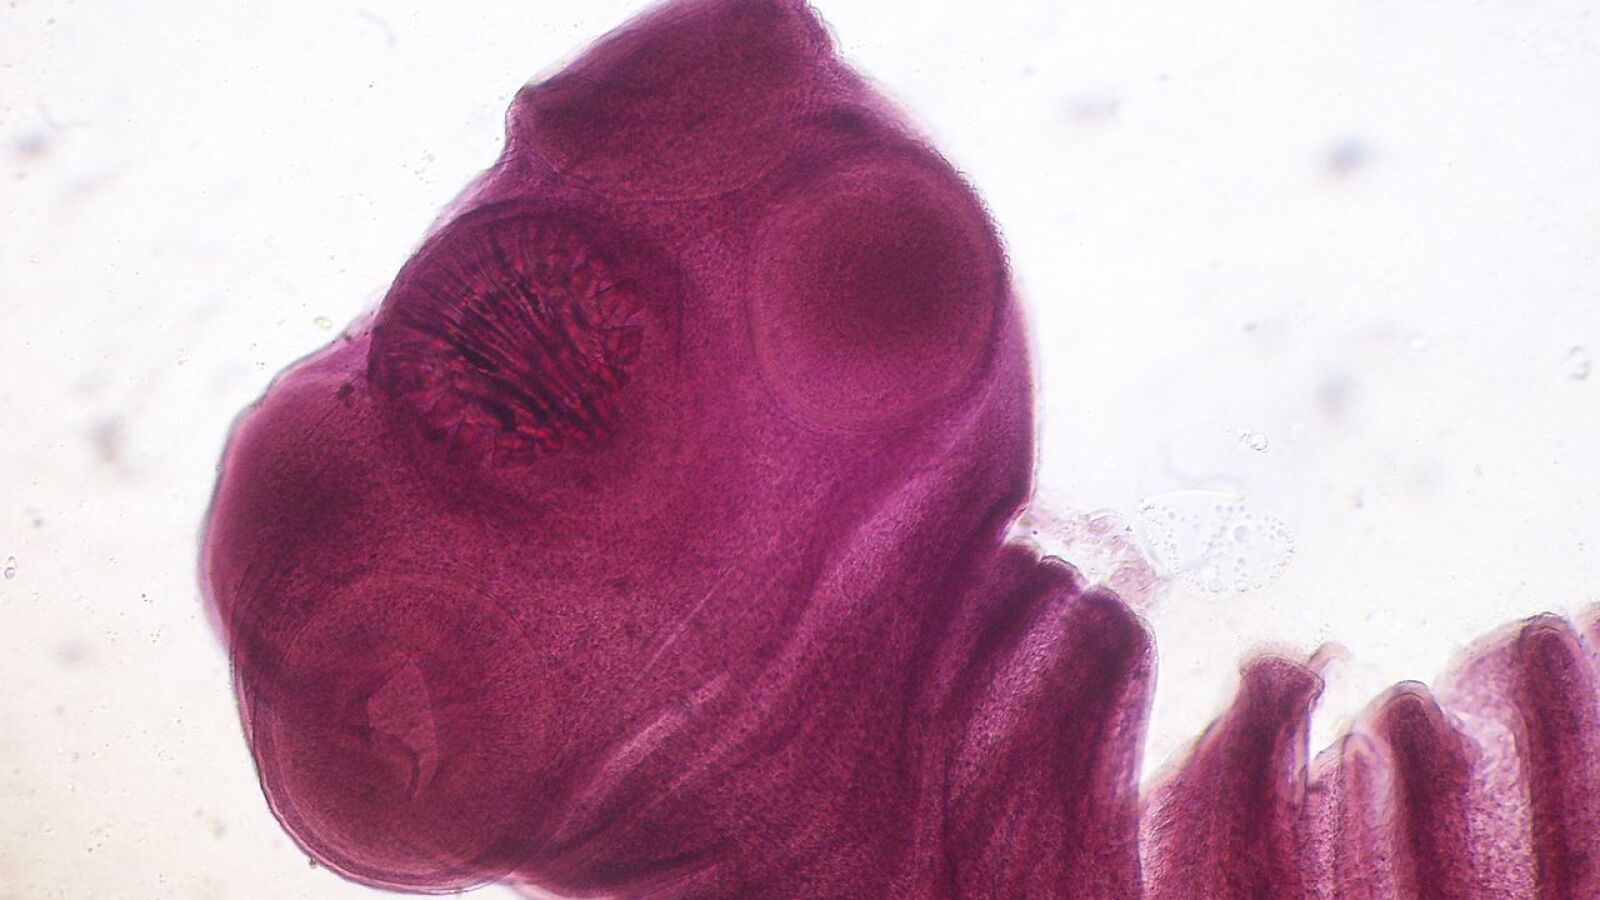

La cisticercosis es una infección de los tejidos causada por los quistes larvales de la tenia del cerdo Taenia solium. Se considera la causa prevenible más frecuente de epilepsia en todo el mundo: provoca el 30% de los casos de epilepsia donde el parásito es endémico. Por lo general, se adquiere al comer alimentos contaminados o a través del agua potable. Los quistes pueden desarrollarse en los músculos, los ojos, el cerebro o la médula espinal.

Los seres humanos pueden contraer cisticercosis por ingestión de huevos del parásito emitidos con las heces de personas infestadas, por vía fecal-oral, o por autoinfestación a partir de la ruptura de los segmentos en que se divide el cuerpo de las larvas adultas alojados en el intestino del mismo hospedador.

En ambos casos, el embrión liberado del huevo penetra la pared del intestino y es transportado por los vasos sanguíneos a cualquier lugar del cuerpo, donde se desarrollan los quistes. La ubicación definitiva suele ser preferentemente el tejido cerebral, aunque también pueden ubicarse en tejido subcutáneo o en órganos como hígado, riñones y ojo.